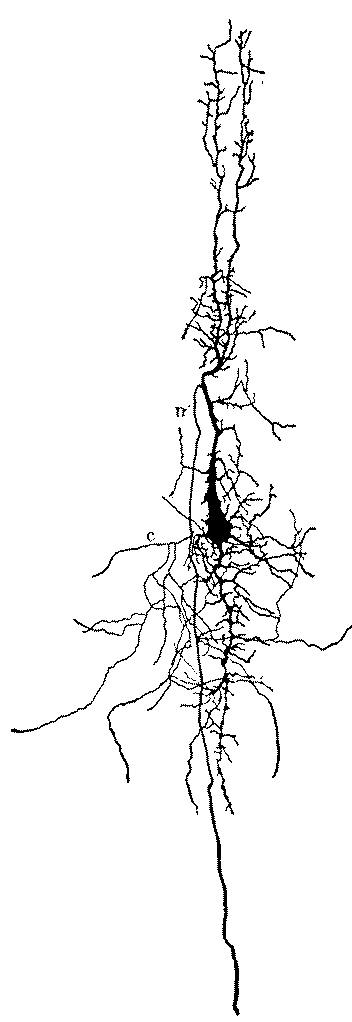

| 2. | Cortex of human brain illustrating complexity of the systems and plexuses of nerve fibers | 109 |

| 3. | Small and medium-sized pyramidal cells of the visual cortex of a child twenty days old | 110 |

| 4. | Series of sections showing the fine nerve endings and branchings of the first and second layer of the visual cortex of a child fifteen days old. | 111 |

| 5. | First, second and third layer of the anterior central convolution of the brain of a child one month old | 112 |

| 6. | Layers of the posterior central or ascending parietal convolution of a new-born child | 112 |

| 7. | Diagram of cells of cerebral cortex | 113 |

| 8. | Scheme of lower motor neuron | 114 |

| 20. | Complexity of cell of the central nervous system | 131 |